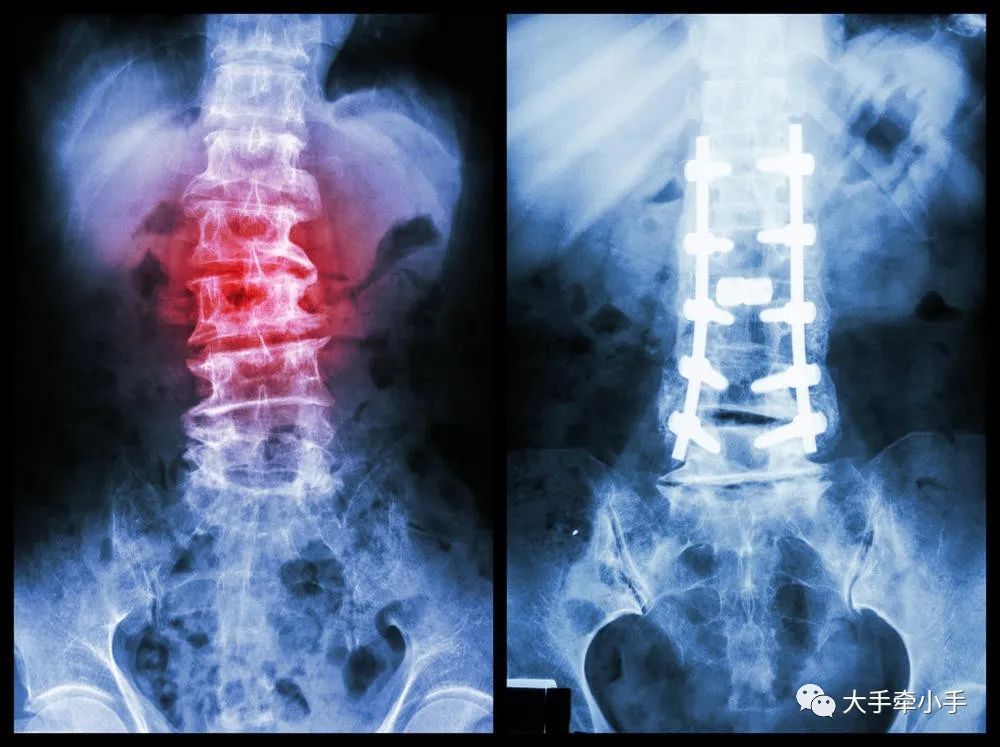

脊柱侧弯是一种脊柱的三维畸形,包括冠状位、矢状位和轴位上的序列异常。一般以拍摄站立位的全脊柱X线片为诊断依据,如果正位X线片显示脊柱有大于10度的侧方弯曲,即可诊断为脊柱侧弯。

轻度的脊柱侧凸可以观察,严重者需要手术治疗。还是那句话,关键是要早发现、早治疗。

首先,说一个常识——脊柱侧弯是不可逆的,也就是只要弯了,就不可能完全变正,所有的治疗矫正,都是为了防止进一步侧弯。